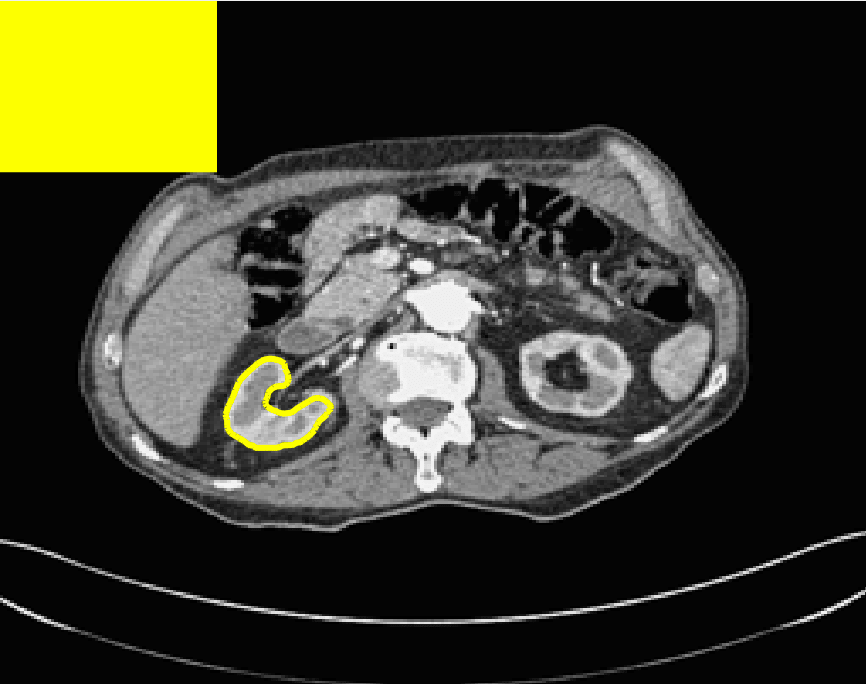

The motivation for this work comes from observing contradictions in using piecewise-constant intensity fitting terms in selective segmentation. Whilst good results are possible with this approach, the exceptional cases lead to severe limitations in practice. This is quite common in medical imaging as demonstrated in Fig. 1, where the target foreground has a low intensity. Given that the corresponding background includes large regions of low intensity, the optimal average intensities for this segmentation problem are and . For cases where , we see that by (1), almost everywhere in the domain . This means that it is very difficult to achieve an adequate result, without an over-reliance on the user input or parameter selection.

for and as defined in (33). This is consistent with respect to the intensities of the observed object and the concept of selective segmentation. In Fig. 3 we see the difference between CV and the proposed fitting terms for given user input on a CT image. For the CT image, the CV fitting terms are near 0 within the target region. This is despite there being a distinct homogeneous area with good contrast on the boundary. This illustrates the problem we are aiming to overcome. With the proposed fitting term this phenomenon should be avoided in cases like this. By defining as in (33) there is no contradiction if the foreground and background intensities of the target region are similar.